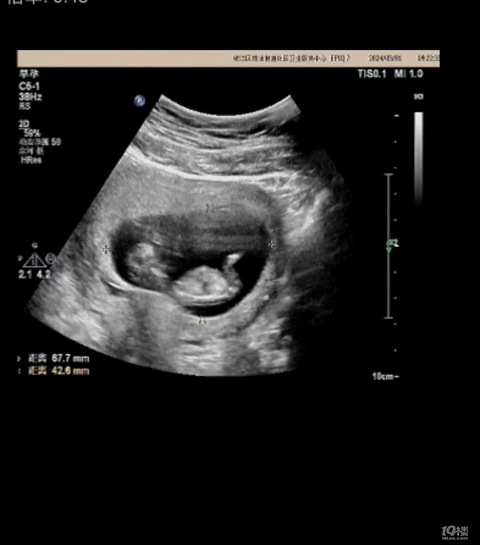

预产期:2022年6月13日 建卡医院:台州市桐屿街道卫生院 产检医院:台州市妇女儿童医院 宝宝小名:腾腾 生产医院:台州市妇女儿童医院 B超照片: